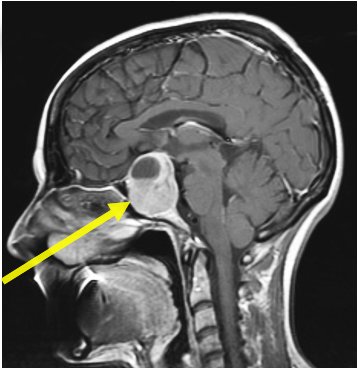

Cirugía endoscópica para tumor en la hipófisis en Barcelona

La cirugía endoscópica para tumor en la hipófisis se realiza a través del seno esfenoidal, un espacio hueco en el cráneo que se encuentra detrás de los conductos nasales (debajo del cerebro), y cuya pared posterior “envuelve” a la Glándula Pituitaria.